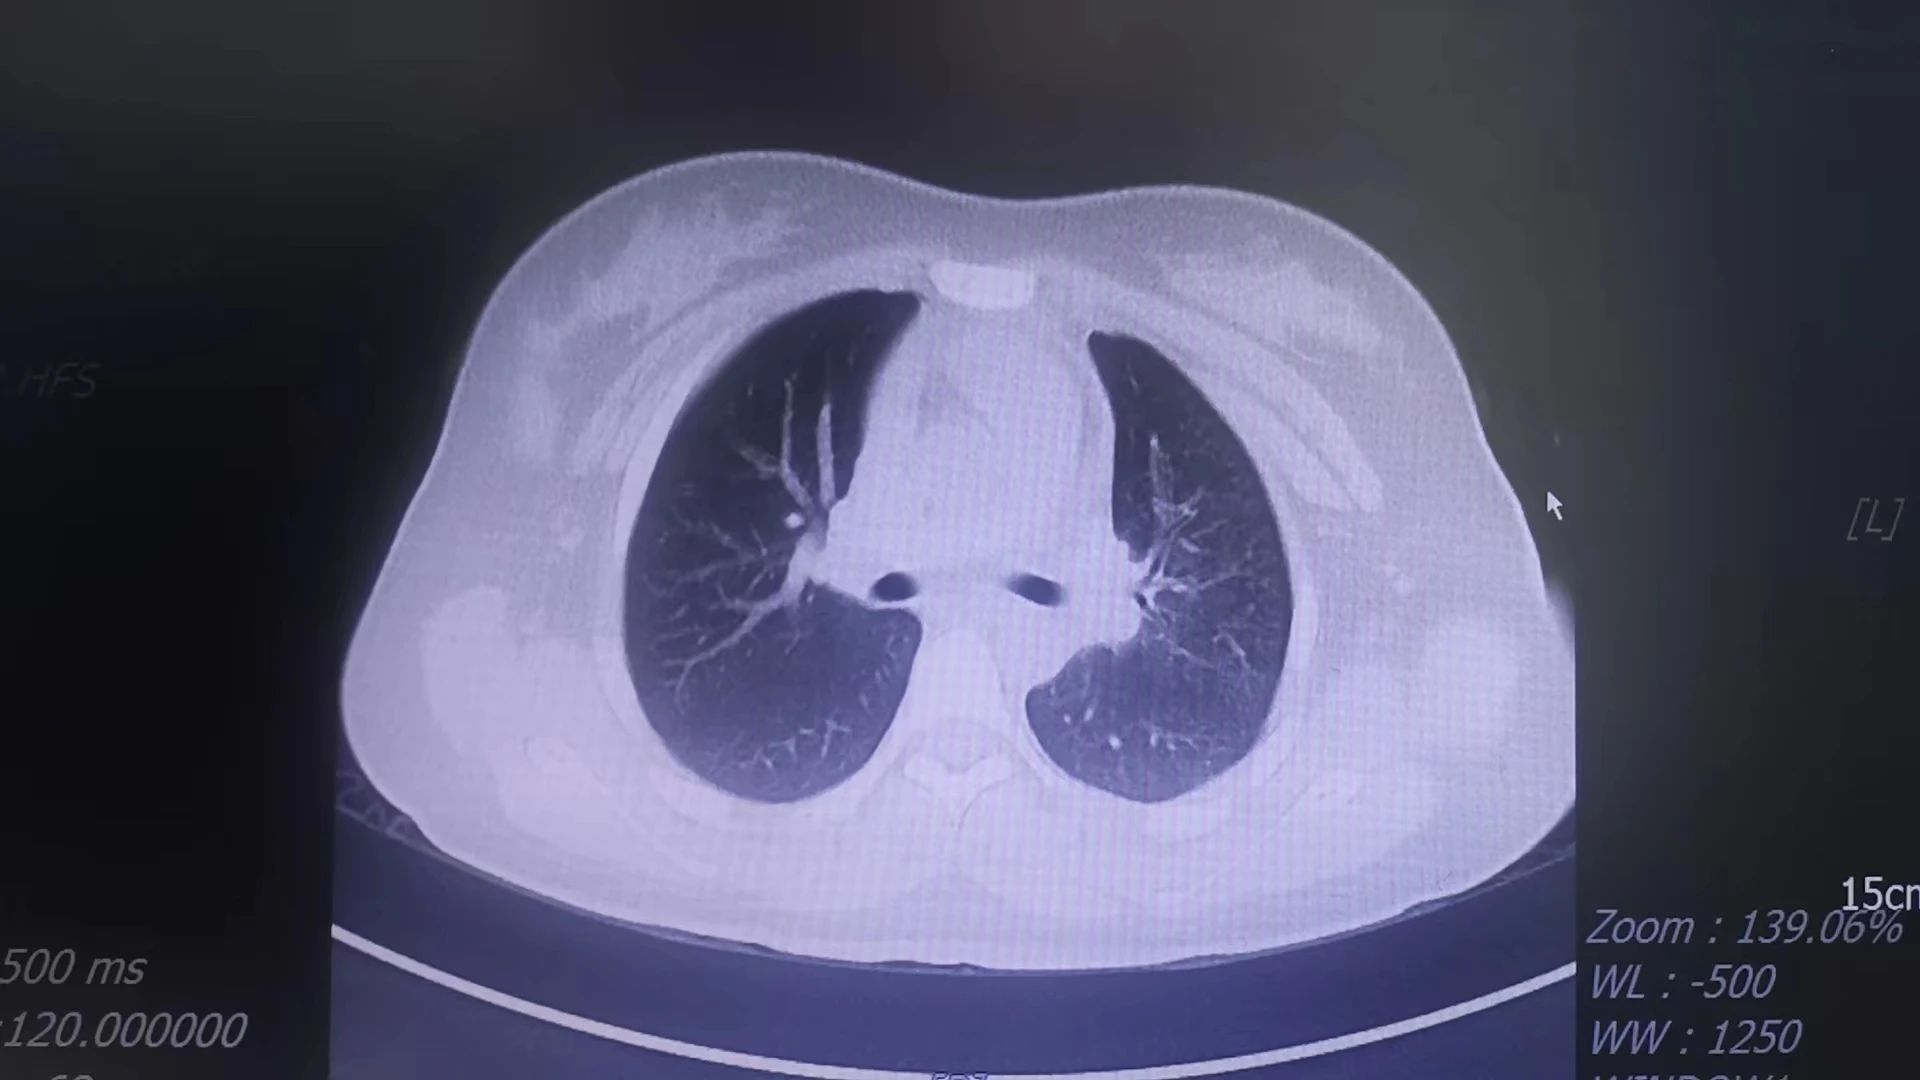

該患兒因“反復(fù)咳嗽1個(gè)月”在當(dāng)?shù)匦l(wèi)生院多次治療后無明顯好轉(zhuǎn),遂就診于我院兒科門診,行肺部CT提示大葉性肺炎、肺不張,兒科主任吳清泉主任醫(yī)師立即將患兒收治入院,并邀請(qǐng)泉州市兒童醫(yī)院呼吸科鄭敬陽教授對(duì)患兒進(jìn)行會(huì)診。鄭教授在充分了解患兒病情并為其檢查后,建議行纖支鏡探查。在征得家屬同意后,兒科傅祥彬主治醫(yī)師在鄭教授的指導(dǎo)下對(duì)患者實(shí)施局麻下支氣管鏡檢查和鏡下肺泡灌洗術(shù),術(shù)中清理了氣管和肺內(nèi)大量的膿性分泌物,手術(shù)歷時(shí)20分鐘順利完成。術(shù)后,患兒生命體征平穩(wěn),在父母及護(hù)士的陪同下安返病房。

術(shù)前、術(shù)后CT對(duì)比